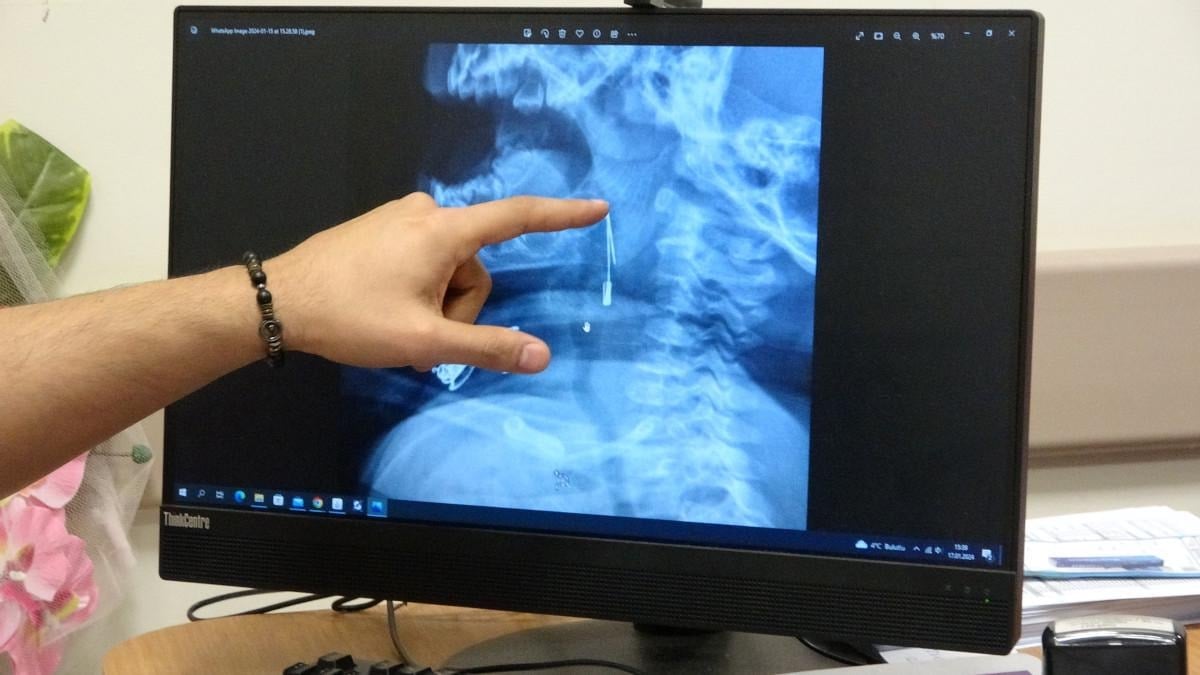

Öksürmeye başlayan minik çocuğun, hastanede çekilen röntgen sonucu çengelli iğneyi yuttuğu fark edildi.

“8 aylık bir bebek, Bitlis’in Güroymak ilçesinden tarafımıza danışıldı. Güroymak ilçesinde çekilen röntgen sonucunda çengelli iğnenin soluk borusunun girişinde olduğunu teyit ettik. Yapılan müdahaleler sonucunda çengelli iğneyi çıkardık. Çıkardıktan sonra iki saat kadar gözlem altında tuttuk hastamızı. Daha sonrasında herhangi bir komplikasyonla karşılaşmadık ve sorunsuz bir şekilde taburcu ettik.”